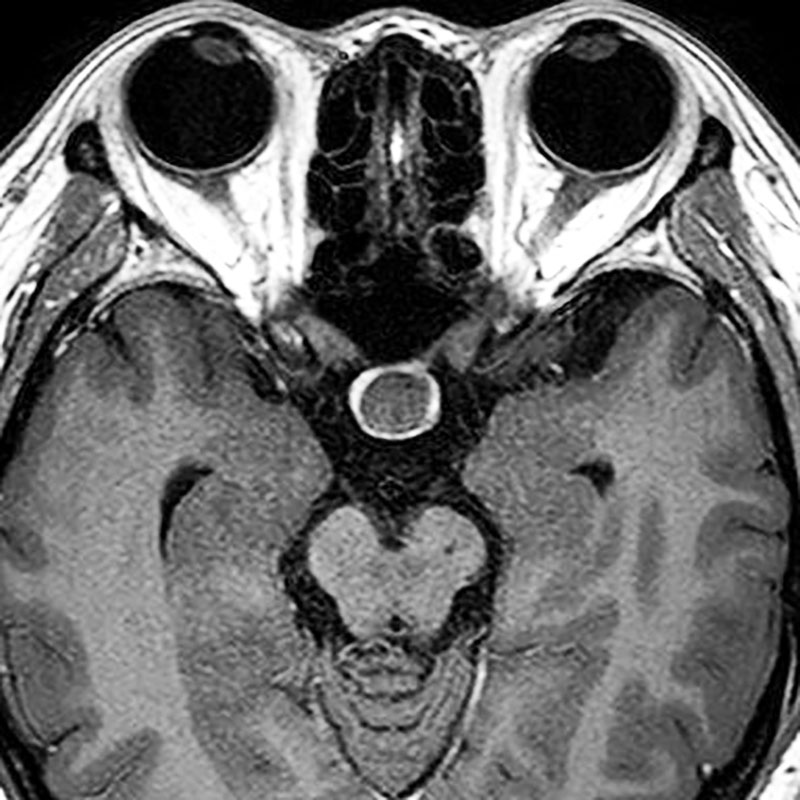

339

'22年10月

50代

右小脳橋角部髄膜腫

頭蓋内腫瘍摘出術

No.’22_96 手術前1

No.’22_96 手術前2